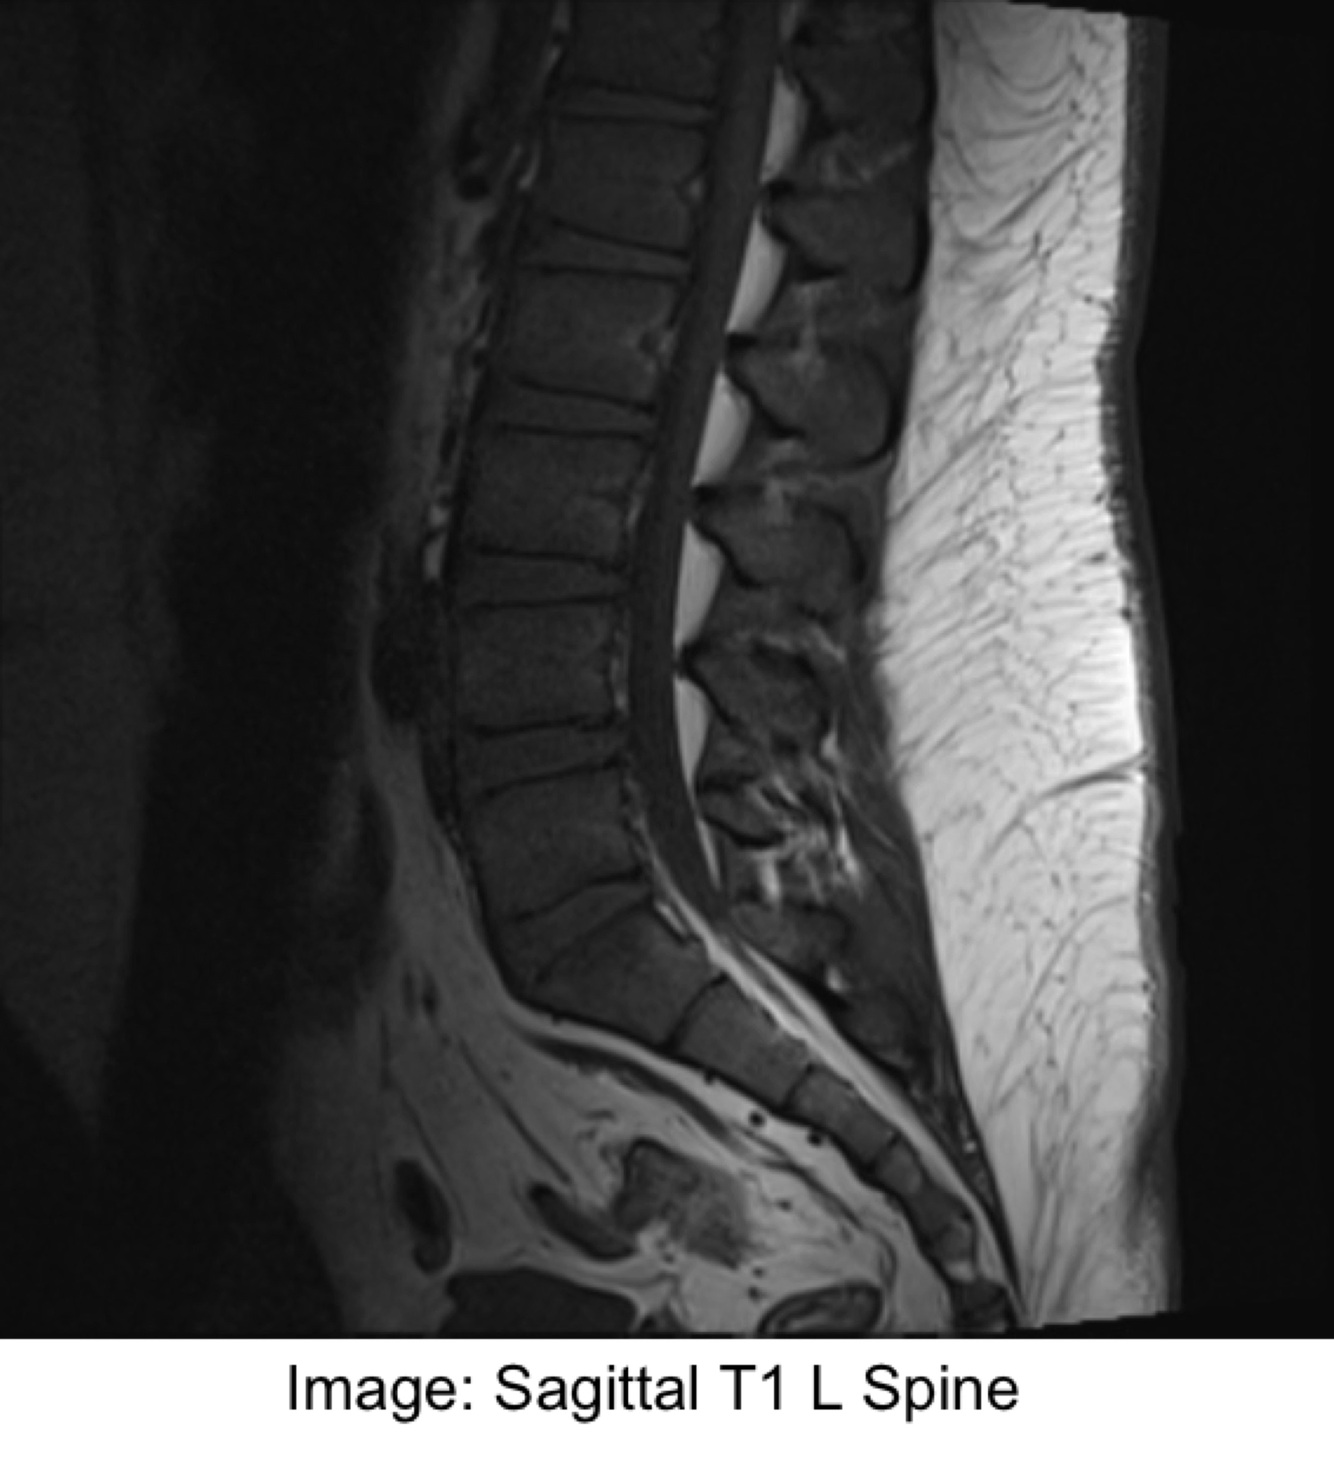

T1 weighted:

An image where the contrast depends predominantly on the differences in the T1 … times between tissues

The TR controls how far each … recovers before the next slice is excited by the next radiofrequency pulse

An image where the contrast depends predominantly on the differences in the T1 RELAXATION times between tissues

The TR controls how far each VECTOR recovers before the next slice is excited by the next radiofrequency pulse

T1 weighted image:

… time (TR) is crucial for T1 contrast

TR controls how far each vector can recover before it is excited by the next … pulse

For T1 weighting, the TR must be … enough so that neither fat nor water have … time to fully return to Bo

If the TR is too long, then both fat and water will fully recover to the … magnetisation

In that case, the difference in T1 contrast can’t be demonstrated in the image

(Short TR = strong T1 weighting

Long TR = low T1 weighting)

REPETITION time (TR) is crucial for T1 contrast

TR controls how far each vector can recover before it is excited by the next RADIOFREQUENCY pulse

For T1 weighting, the TR must be SHORT enough so that neither fat nor water have SUFFICIENT time to fully return to Bo

If the TR is too long, then both fat and water will fully recover to the LONGITUDINAL magnetisation